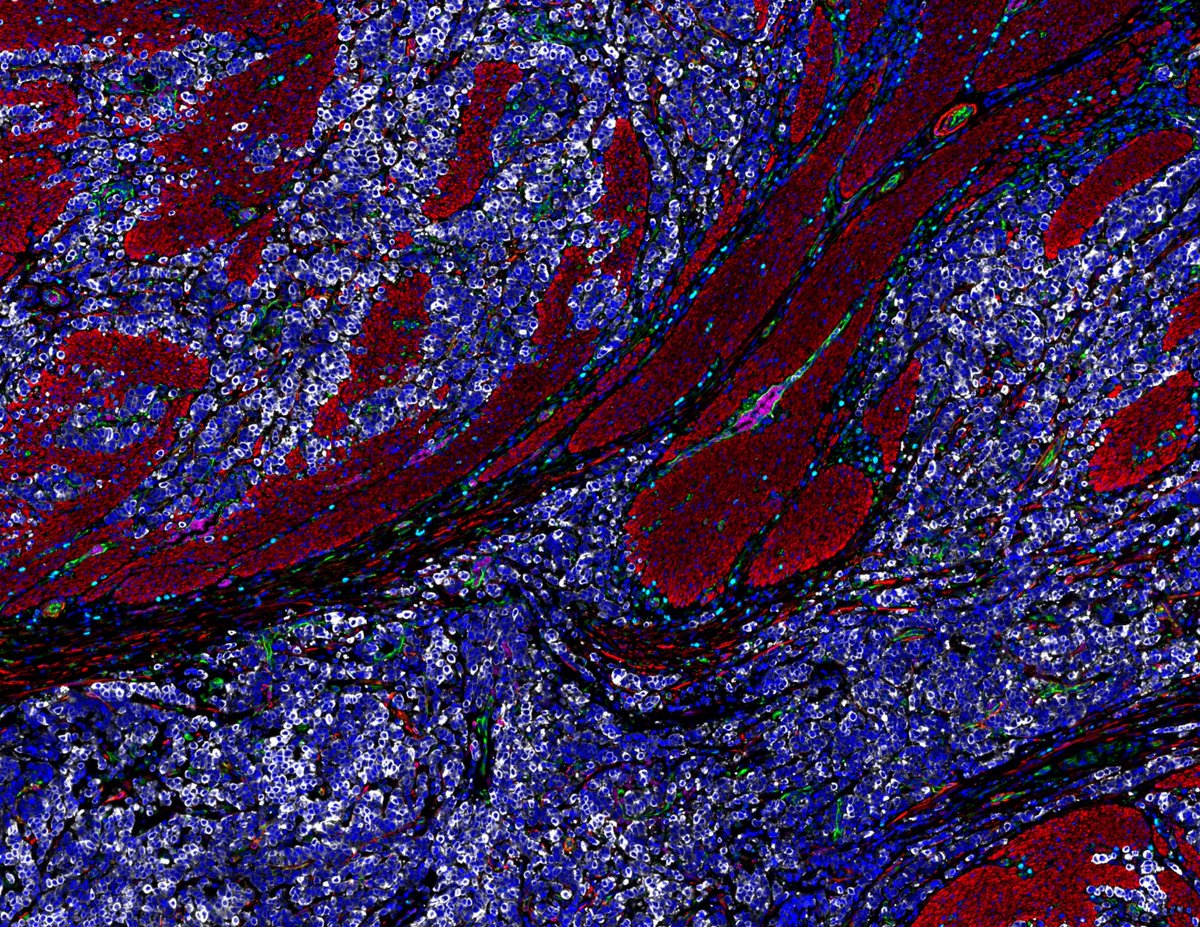

Successful Orion training at @UBC. 🚀 The Poh Lab is using the Orion spatial proteomics platform to map the tumor immune microenvironment in oral cancer.